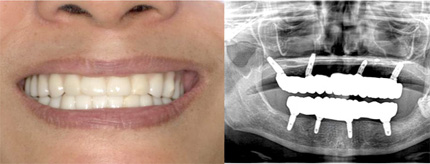

セラミックを被せて治療完了 仮歯を外し、セラミックの歯を被せて、自分の歯のような自然なきれいな状態になります。 |

オールオン4の治療例:1

治療後